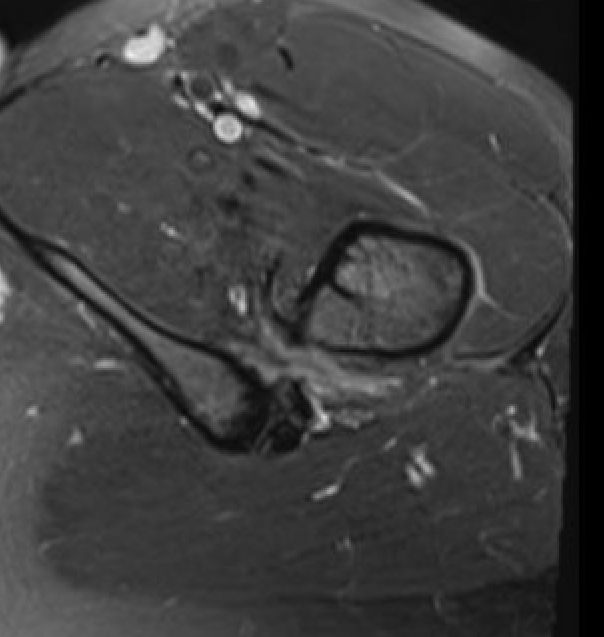

Posterior endoscopic technique

Approach

- make window in quadratus femoris

- medial circuflex flexoral artery superior

- first perforating branch of profunda femoris inferiorly

Advantage

- lesser trochanter is posterior

- preserves anterior insertion of iliopsoas tendon

Disadvantage

- risk of bleeding from medial circumflex / first perforating

- risk injury to sciatic nerve